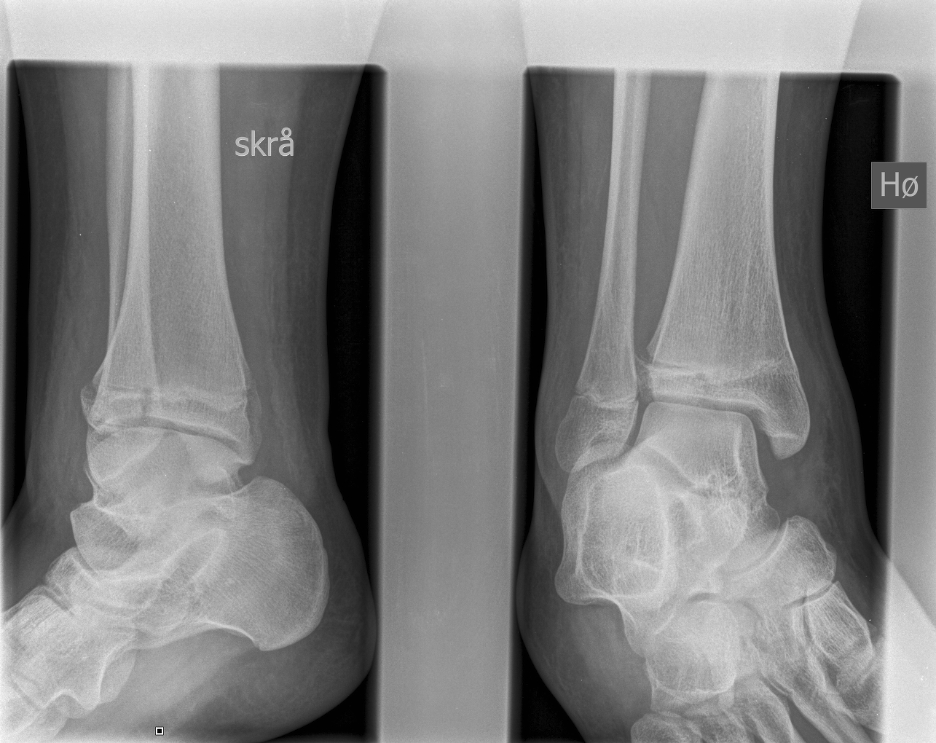

Salter Harris III / Tillaux

Definition

- SHIII of anterolateral distal tibia

- epiphyseal avulsion of AITFL

- supination / ER injury

Incidence

- usually near skeletal maturity

- transitional fracture

- as distal tibial physis is closing

- anterolateral fragment is last to close

Management

ORIF

- reduce articular step / prevent physeal bar

- anterolateral incision to reduce

- either anterolateral 4 mm cannulated screw or

- place screw percutaneously from medial side

Triplanar Fracture

- fracture in coronal, sagittal and transverse planes

- 2, 3 or 4 part

Xray

Type III / Tillaux on AP

Type II on lateral